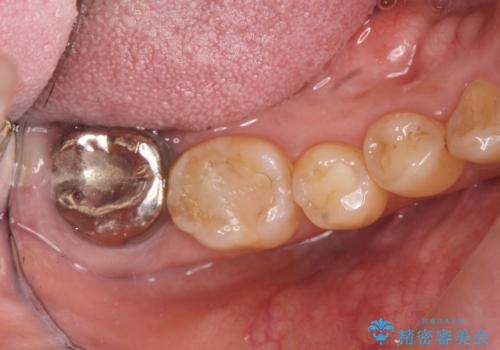

歯周病に対する全体治療

残すことのできない歯は抜去したのち骨造成を含めたインプラント治療を行い、しっかりとした咬合関係を確立していきます。

治療期間はかかりましたが、しっかりと歯周病治療・インプラント治療を行ったおかげで歯周病の状態は非常に良くなり、安定した咬合関係を確立することができました。